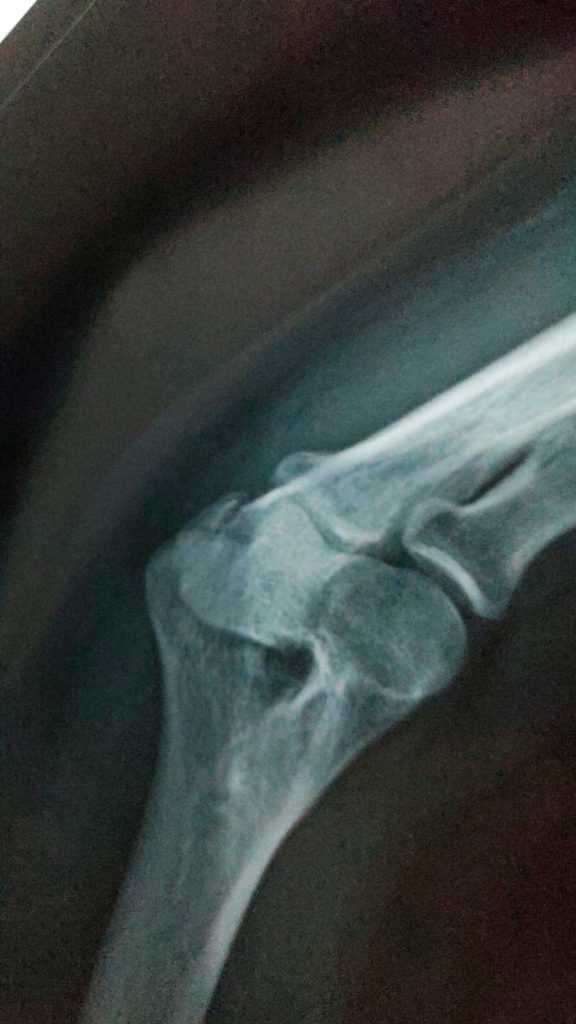

Cuando Ana Ginelly recuperó la conciencia, sólo era capaz de percibir el intenso dolor en su brazo; más tarde se le diagnosticó una fractura de cúbito.